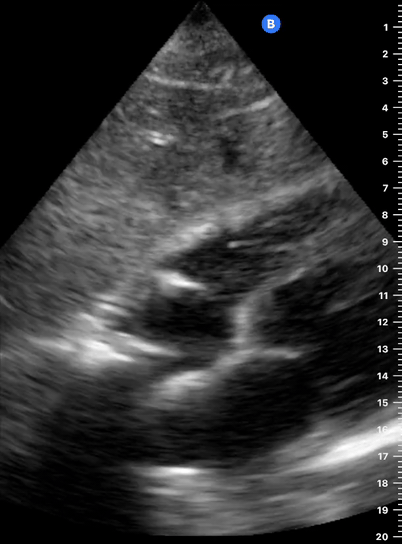

A correct PLAX view will align with the heart’s long axis, producing a sagittal cut. On the screen, from the top, we see the right ventricle, the interventricular septum, the left ventricle with its outflow tract, the aortic valve and aortic root, and the left atrium. It is essential to look for the descending aorta, which appears in a transversal cut deeper to the LV.

Parasternal Long Axis View: The right ventricle is anterior and appears on the screen closest to the probe. The left ventricle is seen deeper to the right ventricle. Marking dot on the right. The apex of the heart points to the left of the screen.

This cardiac preset differs from the abdominal preset in the display orientation: the image is reversed, and the marker dot is now at the right of the screen, posing a challenge to the novice sonographer. For example, on the parasternal long view, the apex of the heart points to the left of the screen, not the right.